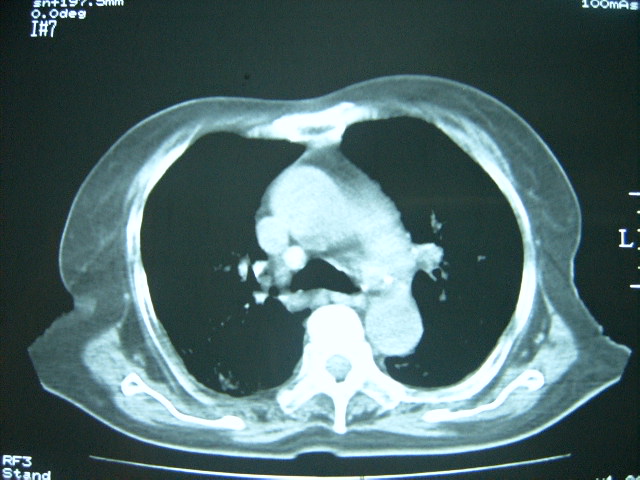

双肺弥漫小结节状高密度,部分融合,边界不清(因为不是hrct,可能为部分容积效应引起),肺门纵隔内未见肿大淋巴结影。无胸腔积液。

双肺弥漫性结节影,双肺上叶为著.纵隔内可见一肿大淋巴结影,密度较高.支持急性血行播散型肺结核.双侧少量胸腔积液.

两肺下叶见高密度钙化灶,支持急性血型播散型肺结核。

两肺弥漫分布之斑点状结节状影,除了血播外,应注意问一下是否有粉尘等病史.但纵隔窗不是很支持.